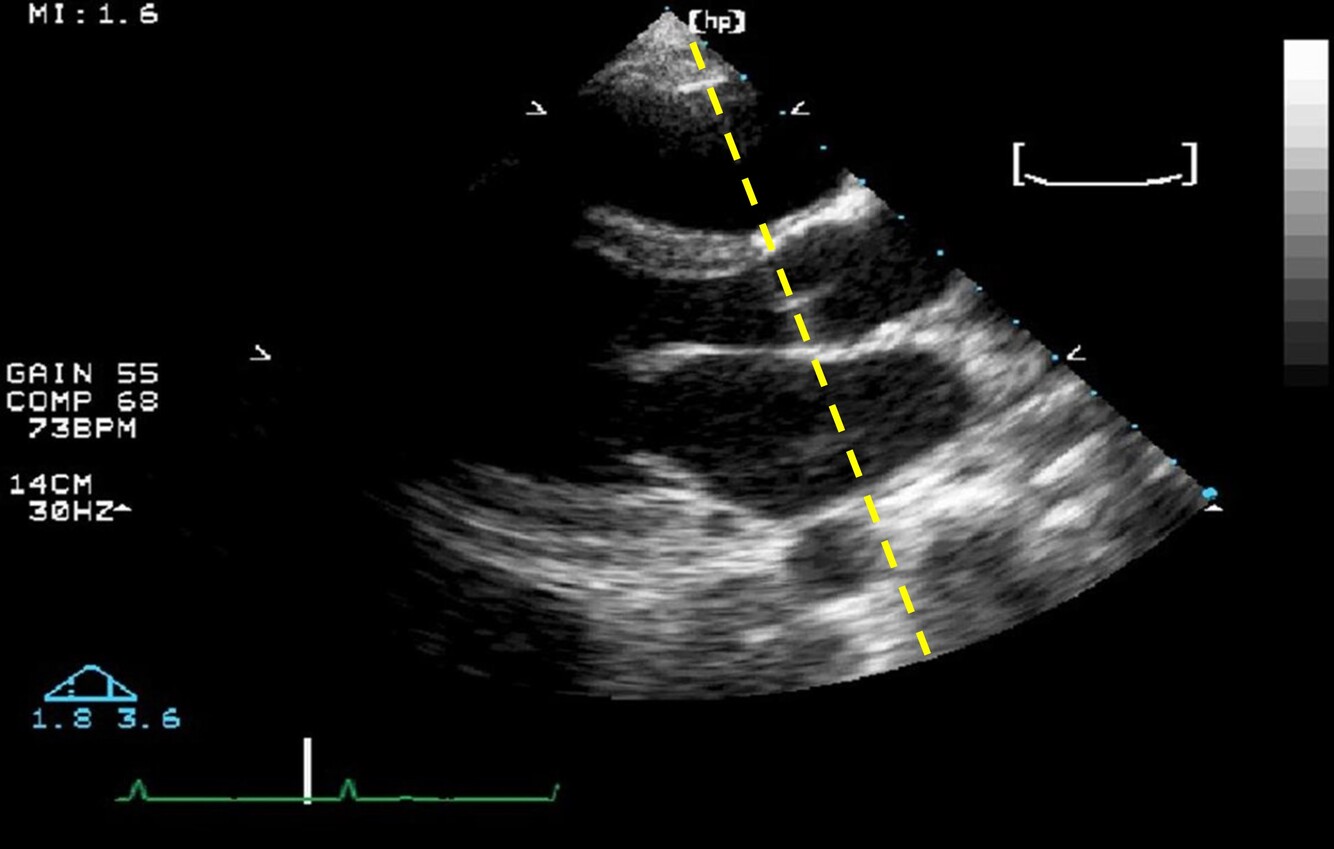

What can Anatomical M-mode correct for? And how?

Poor alignment to any structure by crossing over multiple scan lines. *green line in the image is the AMM, white dotted line is the original M-mode cursor*